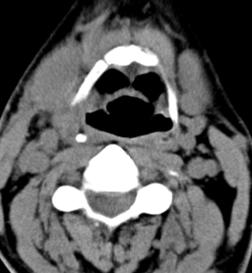

标题: CT17168:会诊,颈部包块 [打印本页]

标题: CT17168:会诊,颈部包块

怎么不传病史呢?右侧颌下腺炎症?

考虑:右侧颌下腺炎症。建议强化。

不排除右侧颌下腺恶性肿瘤可能;建议行进一步检查。

考虑:右侧颌下腺炎症可能。

我也是报的颌下腺炎症。